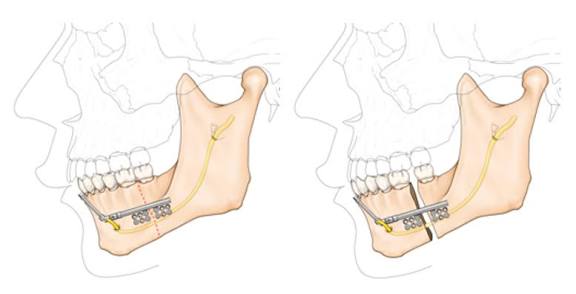

And now imdo, to correct lower jaw